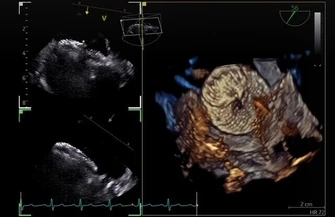

Zabieg nie obywał się w pełnej narkozie, więc pani Barbara wszystko pamięta. - Zerkałam cały czas na monitory. Nie znam się na tym, ale było widać, że coś w sercu jest nie tak jak trzeba, że jest jakaś dziura, która w czasie zabiegu się ładnie zamykała – wspomina pacjentka.

- Ubytek w przegrodzie serca był tak duży, że pacjentka mogła go dostrzec na monitorze podczas zabiegu, nawet nie znając się na medycynie – mówił dr Peruga. – Poza tym był to ubytek mnogi, czyli było kilka dziurek.